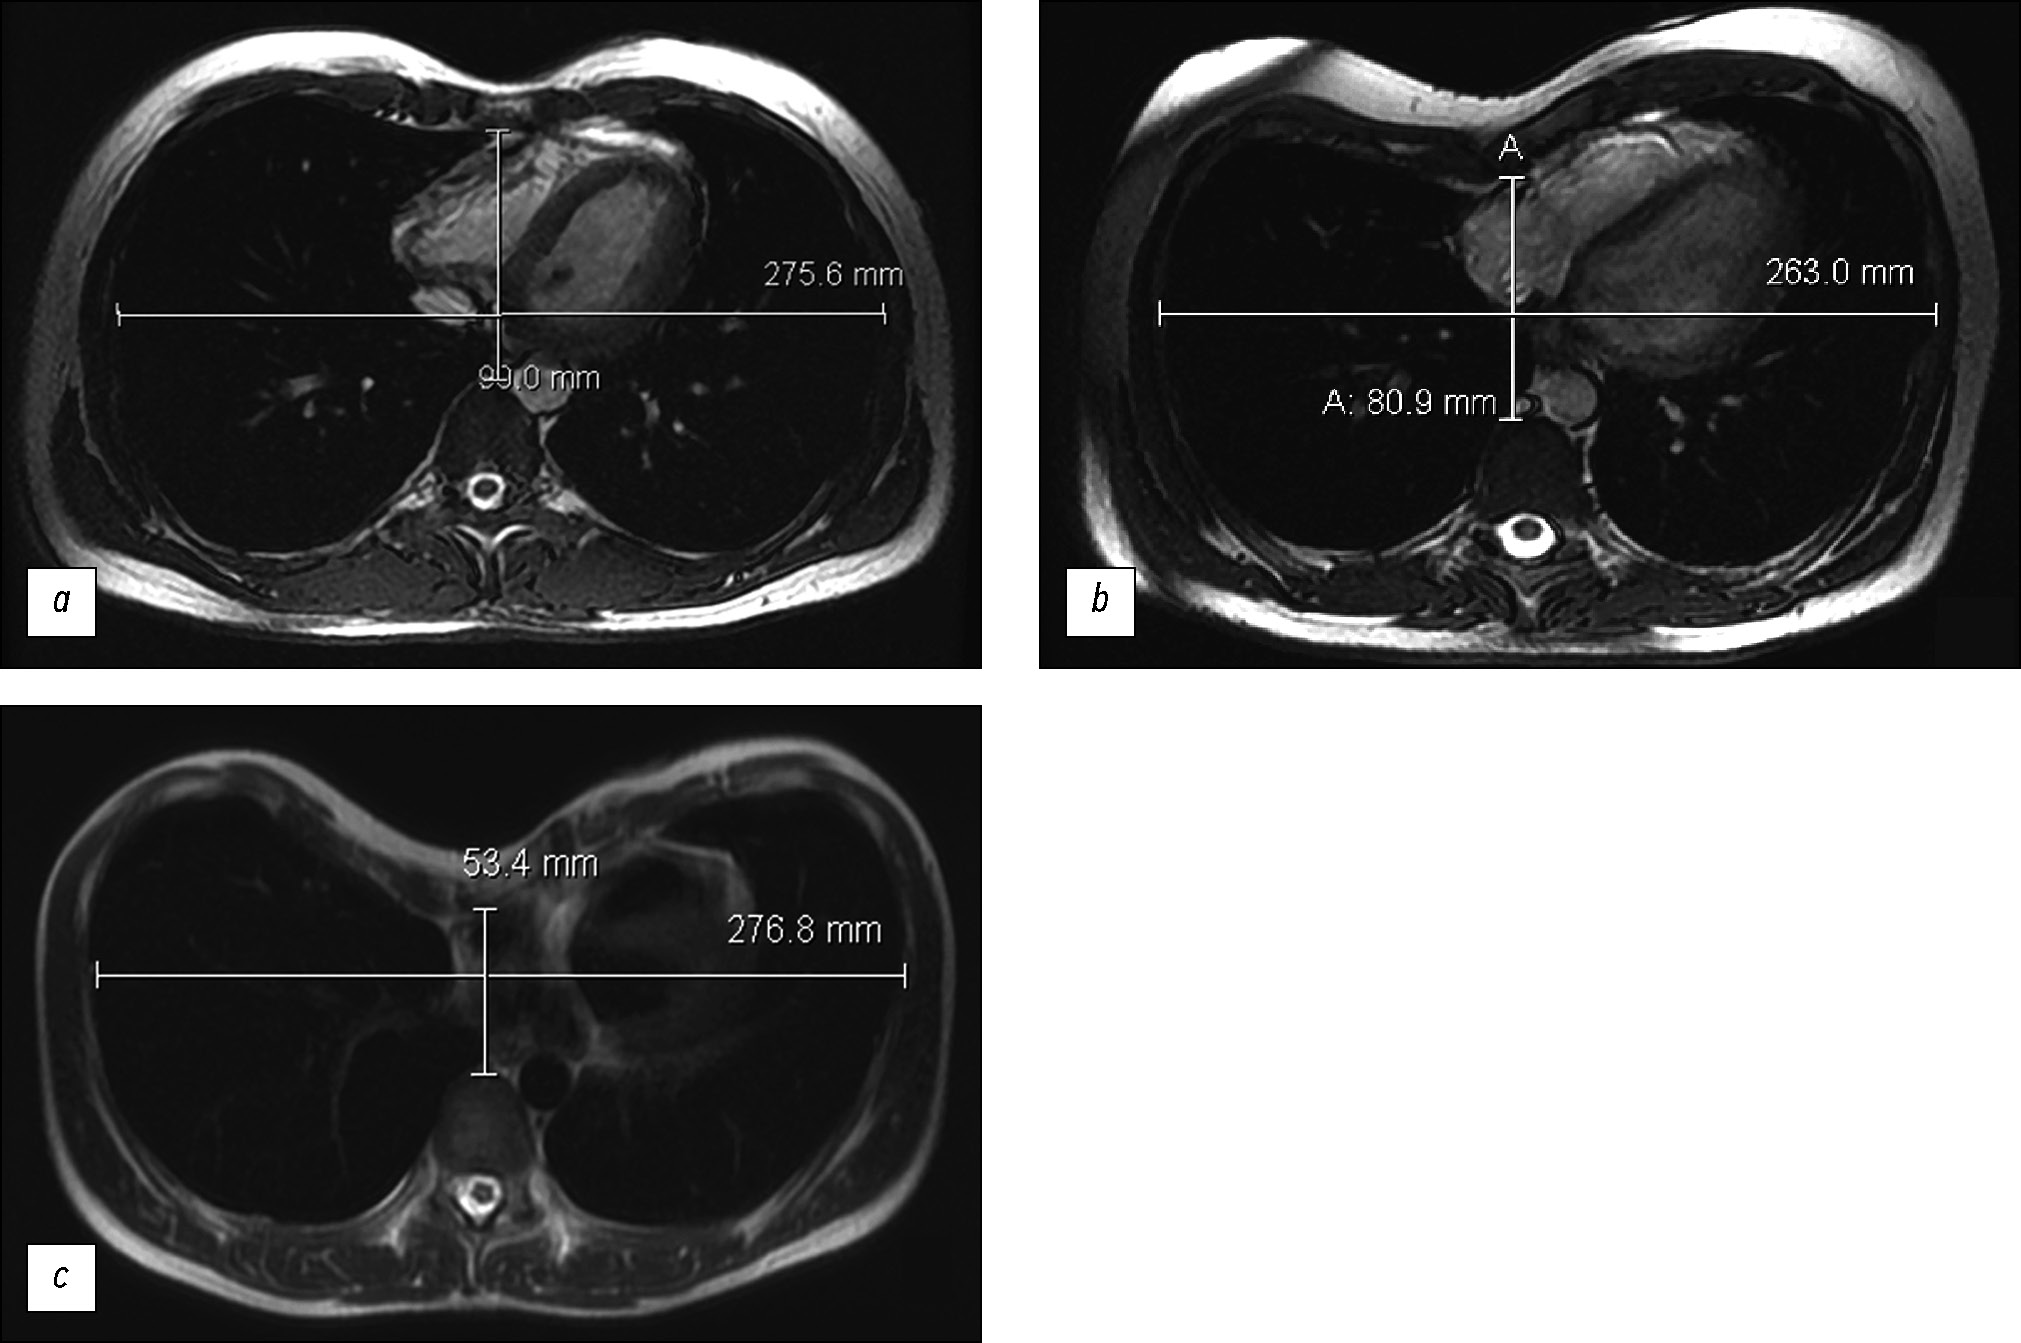

Magnetic resonance imaging in the evaluation of pectus excavatum

Abstract

BACKGROUND: Magnetic resonance imaging is more often used to confirm the presence of pectus excavatum and assess compression changes in the heart at this level.

AIM: To evaluate pectus excavatum preoperatively according to magnetic resonance imaging findings.

MATERIALS AND METHODS: A retrospective evaluation of chest magnetic resonance imaging data of 38 patients (male, n=30; female, n=8) was performed. The average age was 19.9 years (±9 years).Cardiac magnetic resonance imaging was performed on a 1.5-T General Electric Optima MR450w GEM scanner with 2D-FIESTA-C pulse sequences, as well as functional assessment of the left and right ventricles. Parameters for surgical treatment of pectus excavatum were as follows: the Haller index, correction index, and sternum rotation angle. Statistical analysis of the relationship between the Haller index, correction index, and sternum rotation angle and ejection fraction of the right ventricle was conducted. A p-value <0.05 was considered significant.

RESULTS: Moderate and severe pectus excavatum were found in 92% of the cases. No significant Pearson correlation was obtained between the Haller index and right ventricular ejection fraction (inspiratory and expiratory ejection fraction, p=0.777 and 0.798, respectively). The mean right ventricular ejection fraction was 46%. A correlation was noted between the Haller index and the correction index (p <0.05). The rotation angle of the sternum, which required modification of surgical intervention, was detected in 44.7% of patients.

CONCLUSION: Magnetic resonance imaging is an informative diagnostic method for pectus excavatum pectus excavatum without radiation exposure and enables detailed preoperative assessment. A correlation was noted between the Haller index and the correction index (p <0.05). Magnetic resonance imaging revealed a decrease in the ejection fraction of the right ventricle.